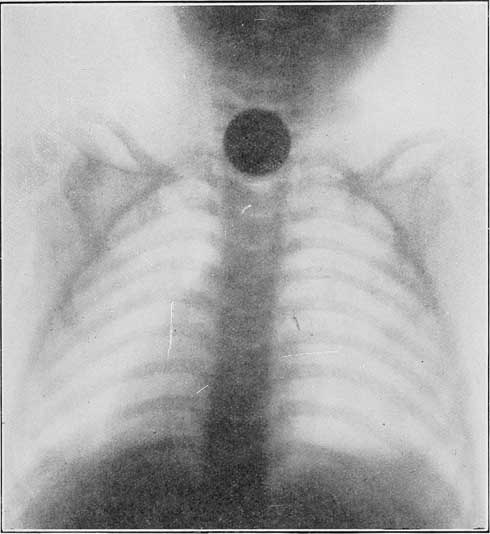

Иллюстрация к книге — Путь избавления. Школа странных детей [i_038.jpg]